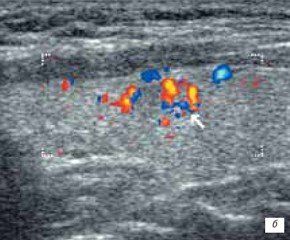

Это метод,технология,это для врача,они себе подсвечивают сине красными такими пятнами(вот я вам картинку нашла)